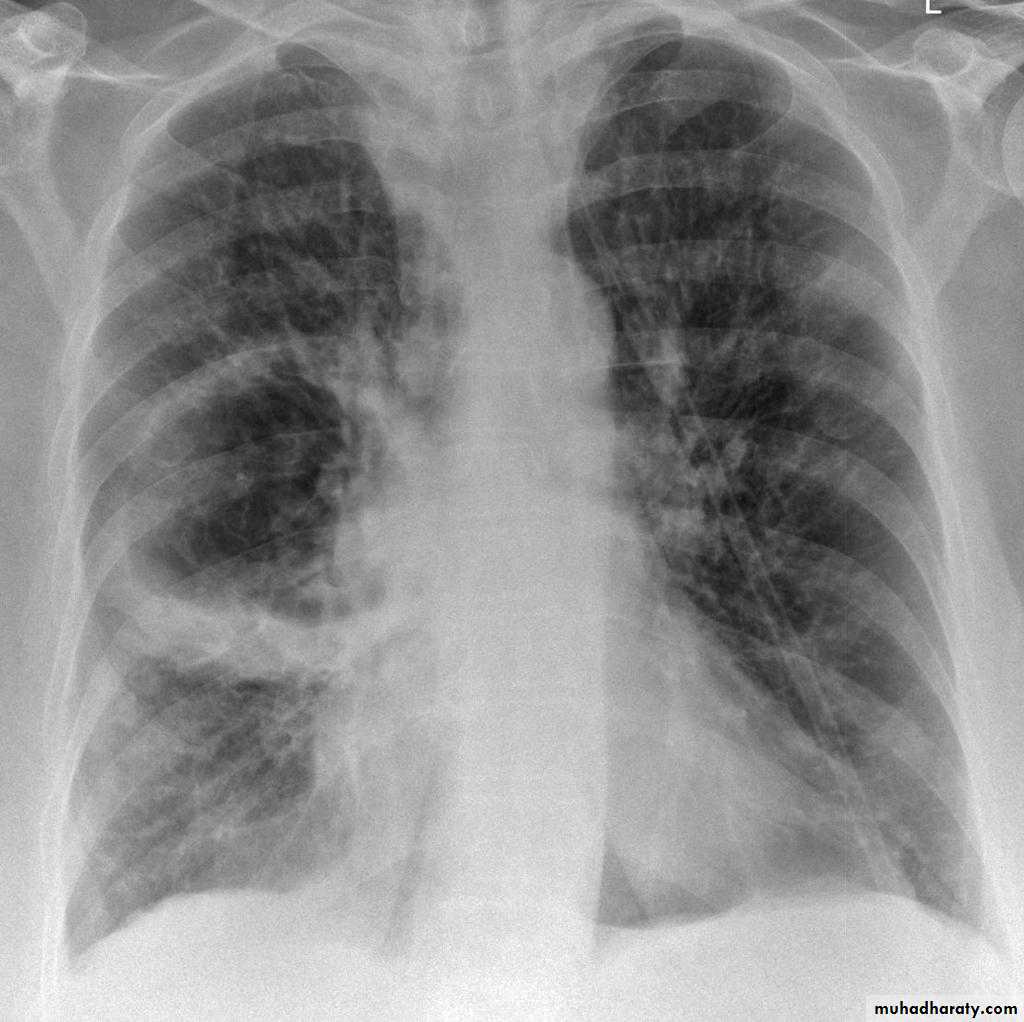

Bronchiactasis

Bronchiectasis refers to abnormal dilatation of the bronchial tree and is seen in a variety of clinical settings. CT is the most accurate modality for diagnosis. It is largely considered irreversibleCauses of bronchiactasias very important to consider

Plain radiograph

Chest x-rays are usually abnormal

1. Tram-track opacities are seen in cylindrical bronchiectasis, and

2. air-fluid levels may be seen in cystic bronchiectasis.

Honey comb shadow

3.Overall there appears to be an increase in bronchovascular markings, and bronchi seen end on may appear as ring shadows .

4.Pulmonary vasculature appears ill-defined, thought to represent peri bronchovascular fibrosis .